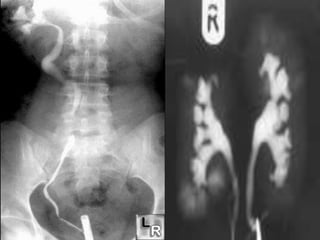

 One method of examining bladder function is by

injecting dye that is visible on X-rays through a

tube (catheter) to fill the bladder. X-rays are taken

while the bladder is full and while the patient is

urinating (voiding) to determine if fluid is forced

out of the bladder through the urethra (normal) or

up through the ureters into the kidney

(vesicoureteral reflux). This study is usually done

with the patient lying on an X-ray table.

 A retrograde pyelogram is a diagnostic X-ray

procedure used in combination with a cystoscopy

to determine the presence of stones, tumors, or

other obstructions in the kidneys and ureters.

 These diseases or medical conditions may be

 An intravenous pyelogram, also called intravenous

urography, is a diagnostic x-ray of the kidneys,

ureters, and bladder. When a contrast dye is

injected intravenously (IV), the urinary tract will

show up very clearly, which is not seen on regular

x-rays. An intravenous pyelogram may be done for

many reasons, including the following: